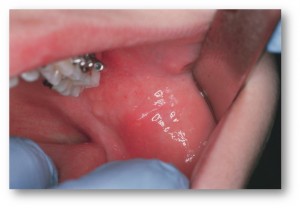

Инкубационный период составляет 2—3 недели. Выделяют три формы течения заболевания: легкая, средняя, тяжелая. Иногда развиваются осложнения. При легкой форме увеличиваются ОУСЖ, они безболезненные, функция их снижена. В дальнейшем может появиться боль и выделение гноя из протока, ухудшение общего состояния. При тяжелой форме возможно гнойное расплавление паренхимы с образованием гнойно-гангренозной формы сиаладенита, требующего немедленного хирургического вмешательства. Иногда наблюдаются осложнения общего характера. При этом эпидемический паротит сопровождается развитием мастита, орхита, панкреатита или миокардита, что требует проведения специального лечения.